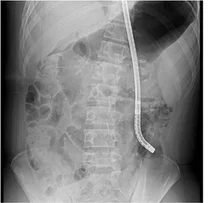

괴사성 췌장염, 내시경적 괴사제거술 치료

고등학생 김모(남·16)군은 지난해 8월 담관석에 의한 급성담관염 및 급성췌장염으로 한림대학교동탄성심병원에 전원됐다. 소화기내과 박세우 교수는 즉시 내시경적 역행성 담췌관조영술 로 담관석을 제거했지만 이미 발생한...